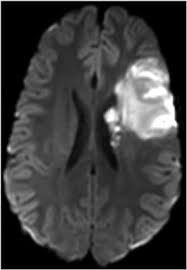

- MRI(자기공명영상): 뇌경색 등 세밀한 뇌조직 변화를 확인할 수 있습니다.

- MRA(자기공명혈관조영술): 뇌혈관의 이상을 확인합니다.